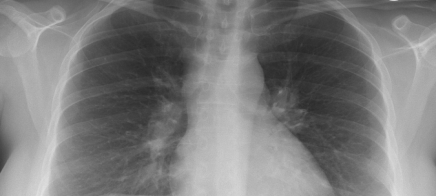

Atopische Dermatitis und Husten: Anamnese, weiterführende Diagnostik und Therapie

Lernziel Anamnese, Klinik, logische Schritte zur Diagnose, Bildanalyse, Therapie.

Was dieser Kurs von Ihnen verlangt Der Husten führt zur diagnostischen Abklärung der Lunge. Diagnostisch öffnen sich damit neue Fenster. Der behandelnde Arzt entscheidet, welche Schritte zur eindeutigen Diagnose führen.